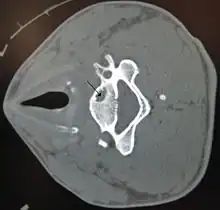

Géode osseuse dans la vertèbre cervicale.

En radiographie, on peut repérer une géode par une image radiographique transparente. -fond homogène -contour tracé par une ligne continue -cavité à contenu liquidien